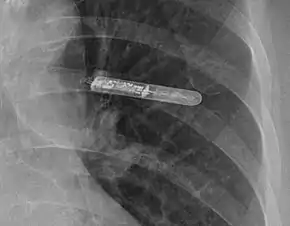

An implantable loop recorder (ILR), also known as an insertable cardiac monitor (ICM), is a small device that is implanted under the skin of the chest for cardiac monitoring, to record the heart's electrical activity for an extended period.[1]

The ILR is implanted by an electrophysiologist under local anesthesia. A small incision (about 3–4 cm or 1.5 inches) is made just lateral to the sternum below the nipple line, usually on the patient's left side.[8] A pocket is created under the skin, and the ILR is placed in the pocket. Patients can go home the day of the procedure with few restrictions on activities.[4] Bruising and discomfort in the implant area may persist for several weeks.